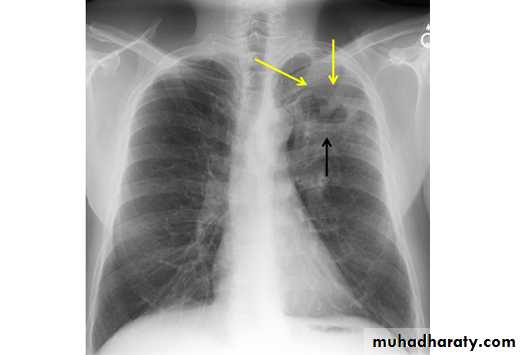

PneumothoraxX-ray pneumothorax

X-ray pneumothorax

X-ray tension pneumothorax